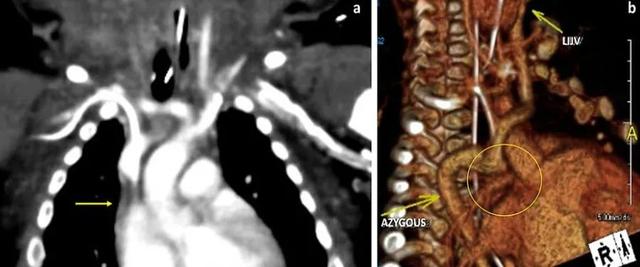

水肿的严重程度有所波动,但始终存在。有时全身有凹陷性水肿,利尿剂和类固醇没有明显改善。因颈部肿胀呼吸困难,CT检查显示右颈内静脉和右锁骨下静脉完全闭塞,颈部和面部两侧皮下水肿明显。胸部CT血管造影证实上腔静脉阻塞,奇静脉侧支代偿性扩张(图)。